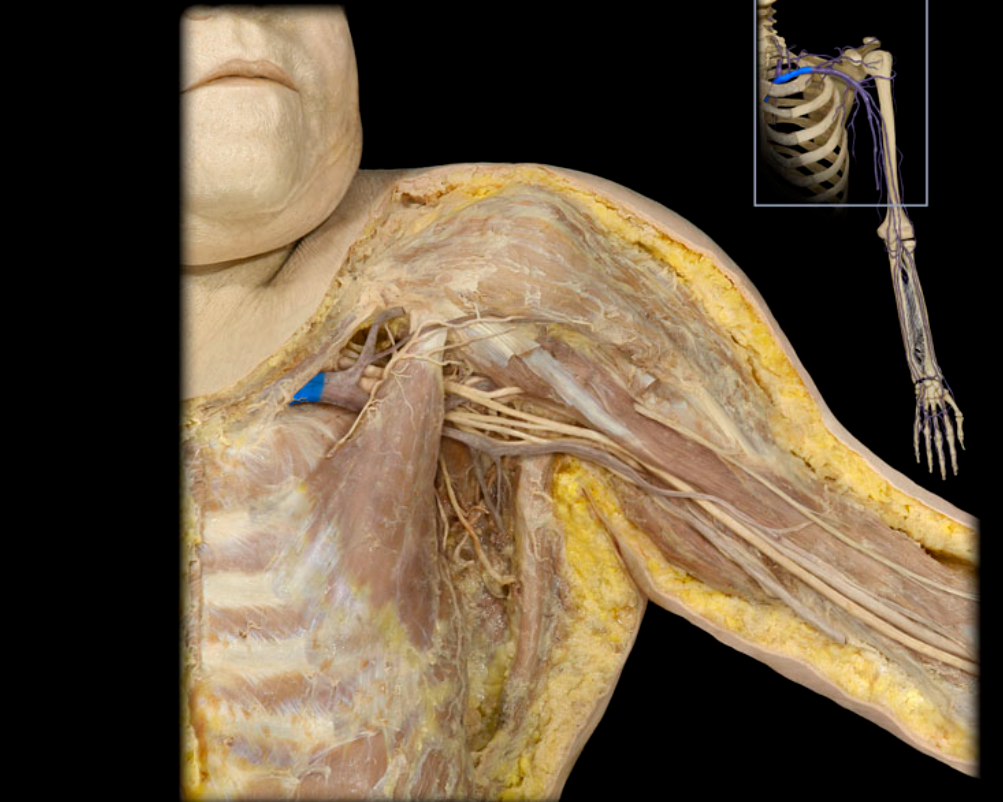

Axillary a.

Basilic v.

Brachial a.

Cephalic v.

Cephalic v. and tributaries

Median cubital v.

Subclavian v.